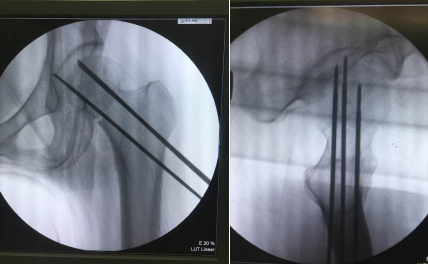

术中,先将患者置于牵引床上闭合复位,C型臂透视见骨折端对位良好;接着,机器人“C臂”透视对患者股骨颈部位行三维扫描,图像被同步传输至骨科手术机器人系统。同时,在导航系统屏幕上规划好钉道。随后,机器人的机械臂将手术工具精确定位到手术位置,套筒指向目的钉道的进钉点。手术小组沿着套筒钻入导引针,确认位置无误,再把空心加压螺钉通过导引针固定,拔出导针。

手术历时50分钟,顺利完成。任海东主任说,以往股骨颈骨折如何精准置钉一直是个难题,但在机器人导航辅助下,手术团队将精确度误差控制在0.2毫米以内。整个手术过程中,透视次数大幅减少,对患者及医护人员的放射保护大大增强。患者术后几乎感觉不到疼痛,换药时看到自己的伤口仅为1厘米时,不禁惊叹:“伤口这么小!真没想到!”